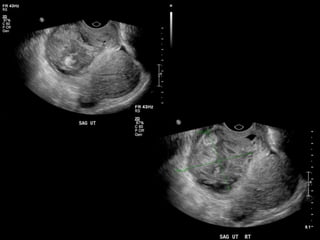

HISTORY

• 40 yo female 8.5 weeks pregant

• S/P D&C for pregnancy implanted at site of

c-section scar

• 6 weeks post D&C patient presents with

heavy persistent bleeding

• For Pelvic US

• HCG = 451 mIU/mL

• What are the findings?

• What is the differential diagnosis?

• What are your recommendations?

• What is the diagnosis?

• What is the treatment?